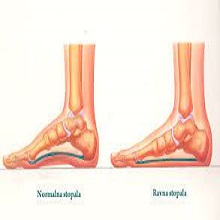

| Једна од веома честих болести колена у општој популацији је остеоартритис. То је хронична болест дегенеративне природе тј. последица је измена у ткивима која сачињавају зглоб, а које настају процесом старења организма. Остеоартритис није специфичан за одређене зглобове, већ може захватити било који. Када је зглоб колена захваћен, то се назива гонартроза. |

| У физиолошким стањима процес изградње и разгрaдање костију је у равнотежи, а остеопороза настаје уколико се та равнотежа наруши (ако се убрза разградња, а смањи изградња костију). |

| Светски дан против остеопорозе обележава се сваке године са циљем да се подигне свест о превенцији, дијагностици и лечењу остеопорозе. Остеопороза представља системски скелетни поремећај који носи повећан ризик од прелома због смањене снаге и густине кости. |